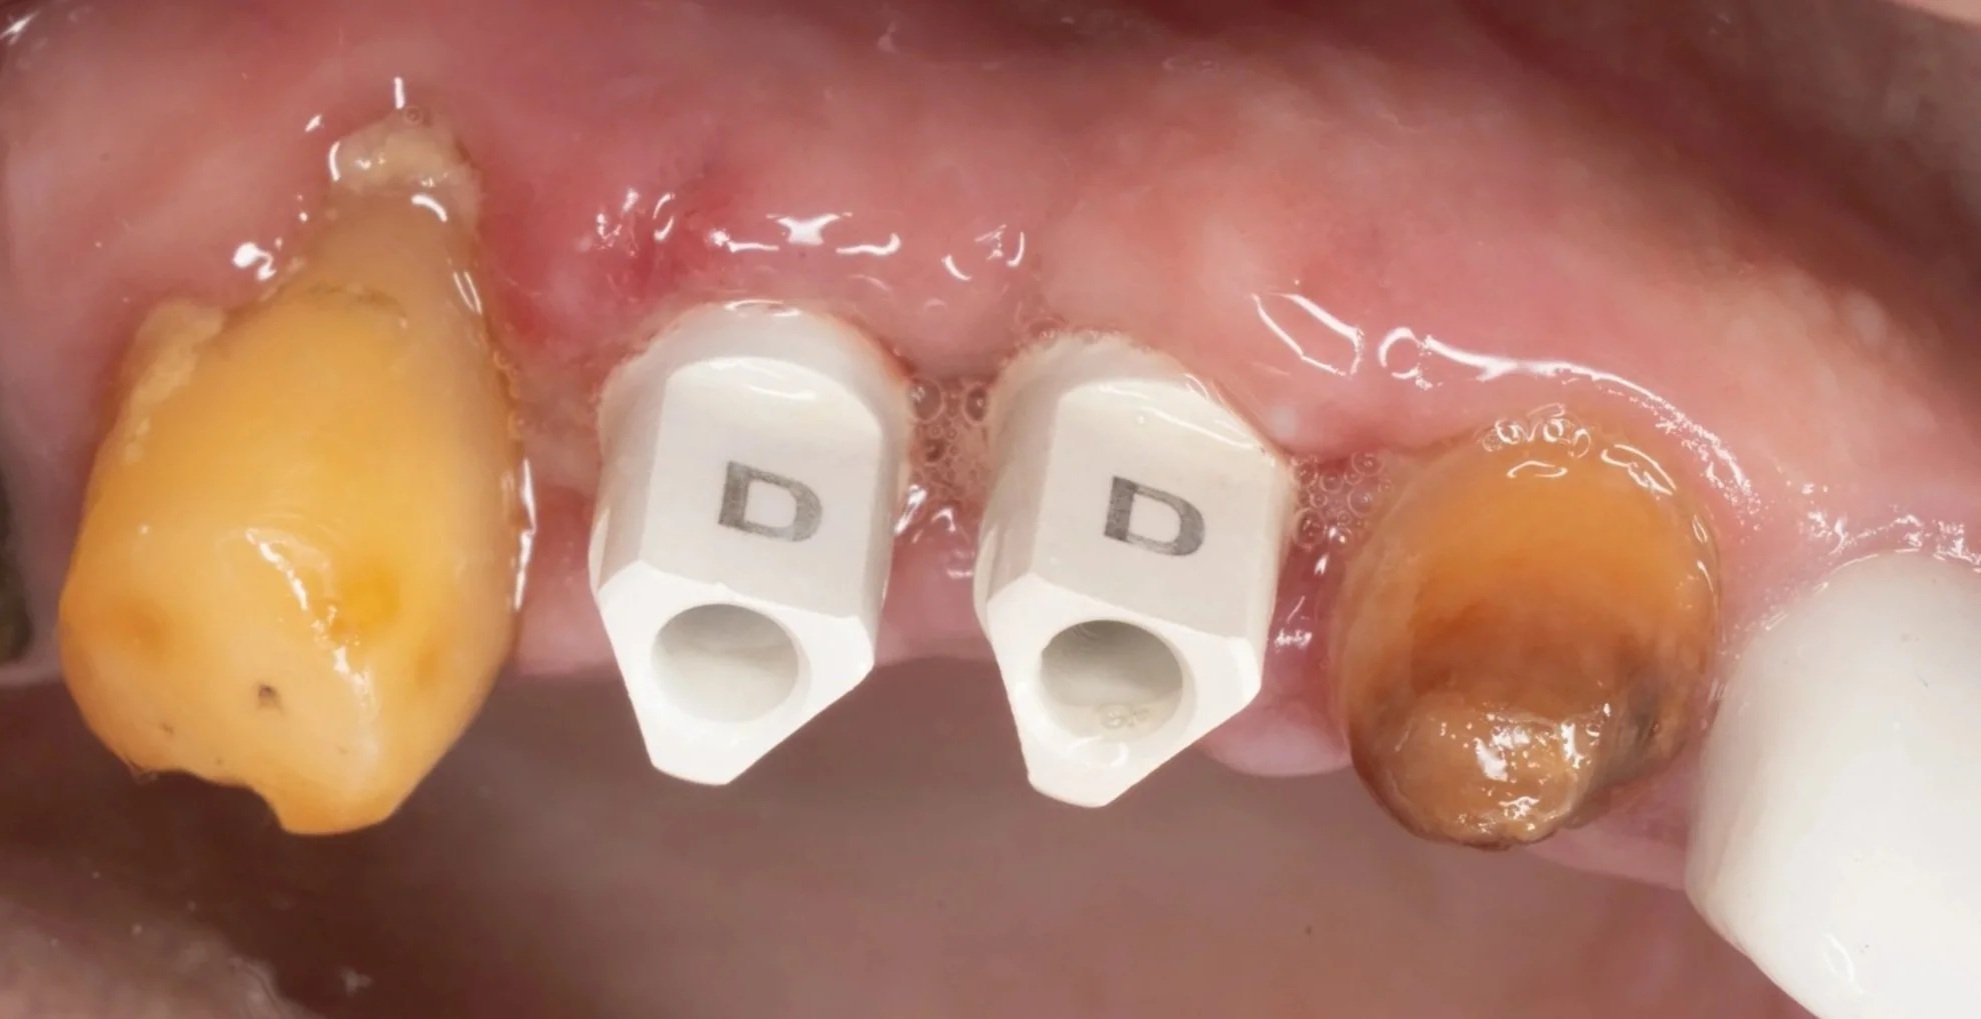

Step 3: Surgical Phase

This phase is the easiest part of the whole procedure, as it is direct application of the previous one. The entire phase took only less than 30 minutes. Post-operative X-rays confirmed perfect implant positioning and parallelism.